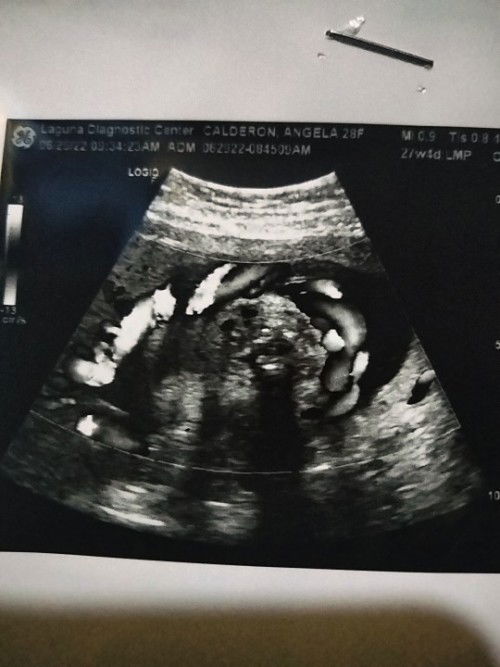

Single cord loop

Hi mga mamsh, I'm 7mos and done with my CAS Ultz. Single cord loop si baby, pero sabi naman ni doc mawawala pa siya pag gumalaw si baby and nagpahilot na din ako π hope everyone is doing great. Goodluck sa mga September due dates! π€°π#1stimemom #pregnancy #firstbaby